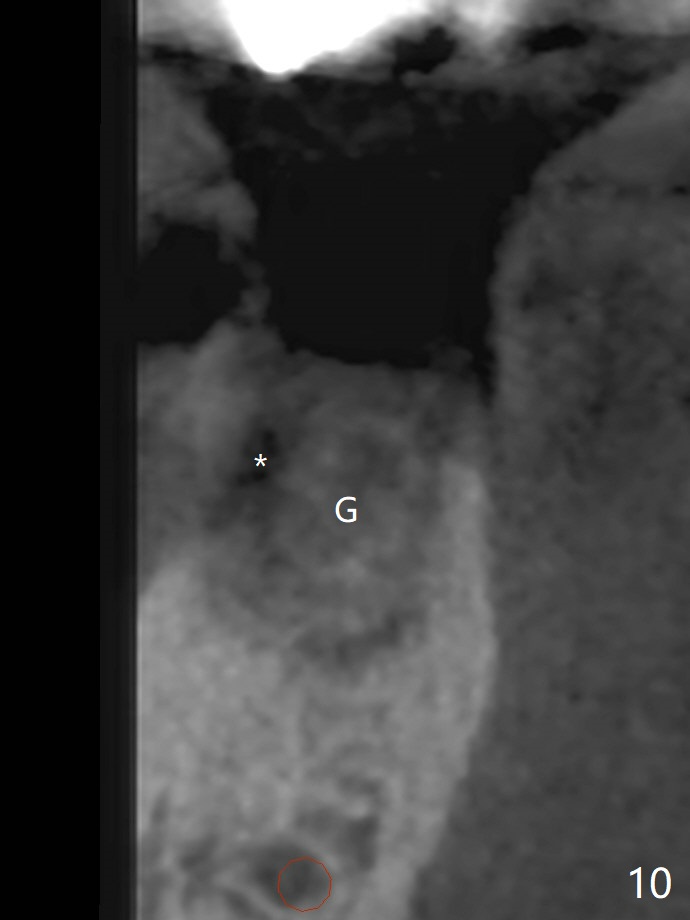

A 88-year-old man returns with pain and swelling (Fig.1), one year after diagnosis of #31 mesial root fracture. After discussion, the tooth is extracted with socket preservation (Vanilla graft mixed with Osteogen, covered with Osteogen plug and Collagen plug, Fig.2,3). The buccal crest is much lower than the lingual one. The socket opening reduces with resolution of 4-0 Chromic gut suture 1 week postop (Fig.4). The wound is wider with foul odor 2 weeks postop (data not shown). The socket and ridge shrink with loss of the bone graft 3 weeks postop (Fig.5). The bone volume reduces with buccal plate collapse 3 months postop (Fig.6,7). Immediate implant and provisional should be able to help restore the lost buccal plate. The buccal plate remains concave 5 months postop (Fig.8,9). The coronal section shows that there is space (Fig.10 *) buccal to the graft (G). A 2.0 mm pilot drill is used to create an initial osteotomy through the graft zone and in the beginning of the native bone (Fig.11,12). Use bone expanders (Fig.13 E) to push (arrowheads) and condense the graft bone and close the buccal gap. The apical portion of the osteotomy requires regular drills (Fig.14 D).